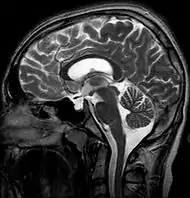

- МРТ головы.

В современных реалиях магнитно-резонансная томография (МРТ) является безопасным и высокочувствительным методом визуализации хиазмально-селлярной области[22][23][24]. Данный метод позволяет проводить исследования в любой плоскости тонкими срезами в 1—1,5 мм, обладает высоким тканевым контрастом, отсутствием артефактов от костных структур черепа.

Для «пустого турецкого седла» характерна триада симптомов:

- наличие цереброспинальной жидкости в полости турецкого седла, о чём свидетельствуют зоны однородного низкоинтенсивного сигнала в режиме T1w и высокоинтенсивного сигнала в режиме T2w, гипофиз при этом деформирован, имеет форму серпа или полулуния толщиной до 2—4 мм, ткань его изоинтенсивна белому веществу мозга, воронка, как правило, расположена центрально;

- асимметричное пролабирование супраселлярной цистерны в полость седла, смещении воронки кпереди, кзади или латерально;

- истончение и удлинение воронки гипофиза.

Помимо основных изменений в параселлярной области МРТ позволяет выявить косвенные признаки внутричерепной гипертензии (расширение желудочков и ликворосодержащих пространств), сопутствующие этой патологии. Разные авторы приводят данные о почти 100 % чувствительности МРТ в диагностике синдрома «пустого» турецкого седла[20][22][23][33].